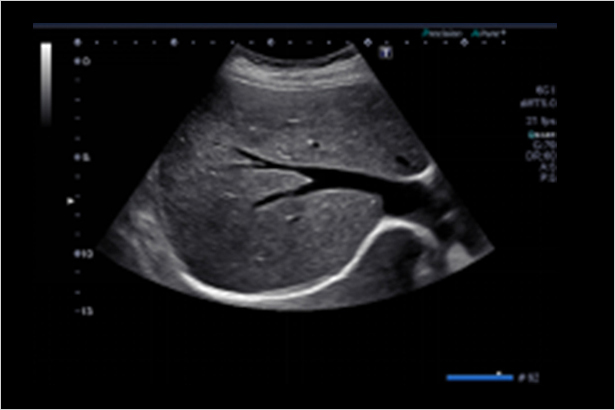

單晶體探頭,配合材料和探頭技術的升級,讓探頭適應臨床操作,并具有良好的圖像

Aplio超聲配備全面的探頭,滿足術中、腔內、經食道心臟成像等多種應用